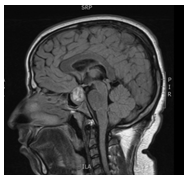

A 31years old man presented to the emergency department with five days history of severe headache accompanied by nausea, dizziness, and blurred vision. The patient’s past medical history was unremarkable and was not on any medications. He is married with 3children, the youngest is 3years old. On physical exam, he was hemodynamically stable with no orthostasis, conscious, oriented and in moderate pain distress (5/10 on pain scale chart). His central nervous system exam showed normal mini-mental status, cranial nerves examination was normal with preserved visual fields. His presentation prompted a brain MRI which showed pituitary macroadenoma with a suprasellar extension (Figure 1) with hemorrhage suggestive of pituitary apoplexy. Hormonal profiles is shown in Table 1, consistent with panhypopituitarism due to non-functional pituitary macro-adenoma with apoplexy. The decision for conservative management was opted for in keeping with the severity of the presentation. He improved and discharged 2days later on hydrocortisone and levothyroxine. However, a few days later he expressed a major concern of diminished libido and sexual dysfunction. At this point, Cabergoline 0.5mg orally twice weekly (off-label) was started with an improvement in his sexual functions within a few days, recovering his pituitary functions (off hormonal replacement). Follow-up MRIs (Figure 2) showed marked shrinkage of the macroadenoma which completely resolved in the most recent image (Figure 3) two years later.

Figure 3 After two years marked shrinkage of the macroadenoma